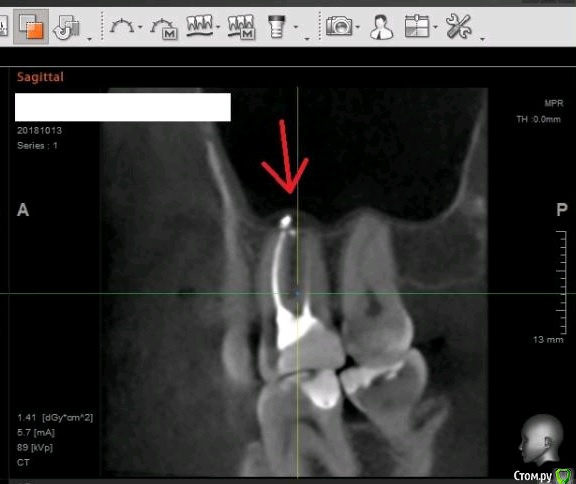

usilitel Опубликовано 4 декабря, 2018 Поделиться Опубликовано 4 декабря, 2018 (изменено) 10 месяцев назад депульпировали верхнюю 6-ку, с тех пор мучаюсь неврологическими симптомами (онемение, давление, зуд). На снимке с зубом всё нормально. Возможная причина - небольшое количество материала вышло в гайморову пазуху (но осталось под слизистой). Я думаю что этот материал мог задеть нерв, отсюда и симптомы. Зуб вырывать врачи отказываются, т.к. показаний к удалению нет. К тому же может не помочь.Хочу вынуть материал из гайморовой пазухи, но непонятно как это сделать. Прошу совета.Возможный варианты:1) Оставить всё как есть. Меня этот вариант не устраивает, т.к.: 1) материал может быть причиной проблем с неврологией, и его удаление может решить проблему. 2) зуб все равно рано или поздно придется удалять, не хотелось бы чтобы после удаления зуба в организме осталось инородное тело.2) Вынуть эндоскопом сверху. ЛОР сказал что так сделать нельзя, т.к. поскольку материал под слизистой - сверху его не увидишь. Правда можно содрать слизистую и всё-таки достать материал, но вред от такого действия многократно превысит пользу.3) При удалении зуба вынуть материал снизу. По словам хирурга - стоматолога - это сделать нереально, т.к. для этого придется разрезать перегородку, отделяющую гайморову пазуху, и она потом сама не заживёт.4) Надеяться, что матерал сам выйдет вместе с зубом при удалении зуба. Вариант крайне маловероятный, т.к. при удалении зуба материал практически наверняка останется в пазухе.5) Распломбировать канал, протолкнуть материал дальше в гайморову (чтобы он вышел за слизистую), а потом вынимать сверху эндоскопом. Не уверен что найду терапевта который согласится это сделать.6) Сразу после удаления зуба протолкнуть материал дальше в гайморову (чтобы он вышел за слизистую), а потом вынимать сверху эндоскопом. Не уверен что найду хирурга который согласится это сделать. PSЗуб мне не жалко, всё равно рано или поздно его надо будет удалять. Изменено 4 декабря, 2018 пользователем usilitel Ссылка на комментарий

usilitel Опубликовано 6 декабря, 2018 Автор Поделиться Опубликовано 6 декабря, 2018 выкладываю снимки Ссылка на комментарий